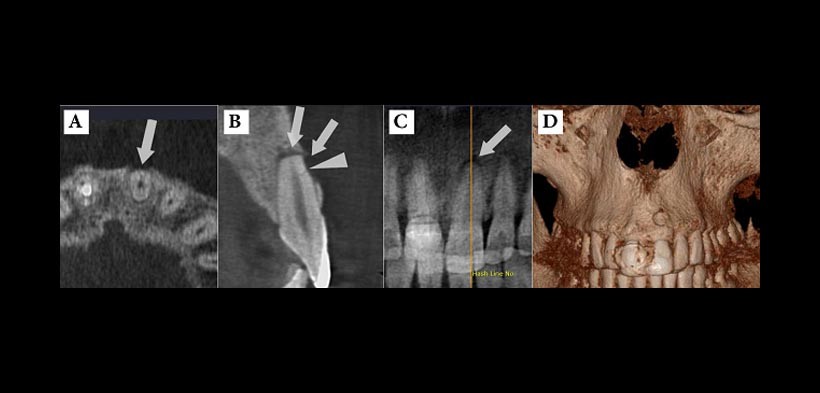

- FRACTURAS RADICULARES: sobre todo fracturas longitudinales la tomografía computarizada presenta una alta capacidad de detección de fracturas verticales en comparación con las radiografías convencionales o digitales (fig. 2).

Figura 2. La CBCT muestra en la figura A) y B) una pequeña fractura radicular horizontal en la superficie vestibular del incisivo central superior izquierdo causada por un traumatismo de impacto; B y C) Tenga en cuenta las dos lesiones periapicales separadas en el área apical (flecha) y adyacente a la línea de fractura (cabeza de flecha) debido a la necrosis del diente; D) La reconstrucción tridimensional de la lesión en la zona vestibular Periapical